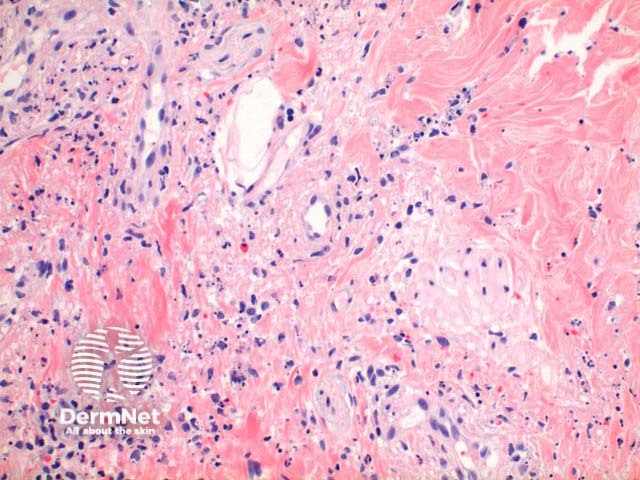

Low power view of leukocytoclastic vasculitis gives the pattern of a busy dermis with a superficial and mid perivascular inflammatory pattern (Figure 1). There is a population of predominantly neutrophils in a perivascular and interstitial pattern in addition to those undergoing extravasation from the vessels (Figure 2 and 3). Leukocytoclasis (neutrophil degeneration) forming nuclear dust is seen in addition to extravasated erythrocytes (Figure 3 and 4). Fibrinoid necrosis of the vessels with fibrin extravasation, while a pathogenic requirement, may be poorly visible or absent in many cases (Figure 3 and 4 demonstrate mild fibrinoid necrosis).

A variable number of eosinophils can be seen and when increased in number may suggest a drug as an underlying cause.

It is important to recognise that the changes vary with the timing of the biopsy, with significant variation seen in the degree of inflammatory infiltrate and vessel wall damage.